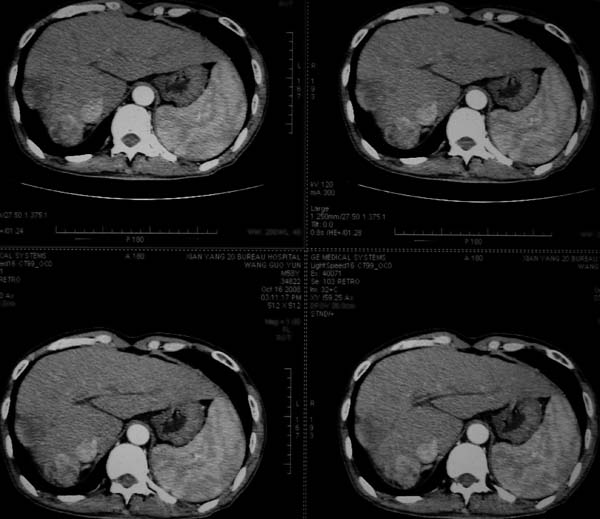

标题: CT16292:男,53岁,上腹部不适2月,B超发现肝内占位病变。 [打印本页]

标题: CT16292:男,53岁,上腹部不适2月,B超发现肝内占位病变。

符合肝ca增强,\"快进快出\";肝叶比例失常,右叶萎缩,肝裂增宽,脾大,肝硬化可能.

肝叶比例失调,左叶增大,肝裂增宽,脾脏增大,门脉增宽,肝右叶包膜下多发结节样阴影,增强虽说强化幅度不大,但还是符合快进快出特点;考虑肝硬化、脾大、结节型肝癌。胆管细胞癌多有延时强化、肝包膜凹陷征、周围胆管扩张等特点,本例明显不符;故不考虑。

动脉期静脉有显影 是否静脉有受侵改变啊